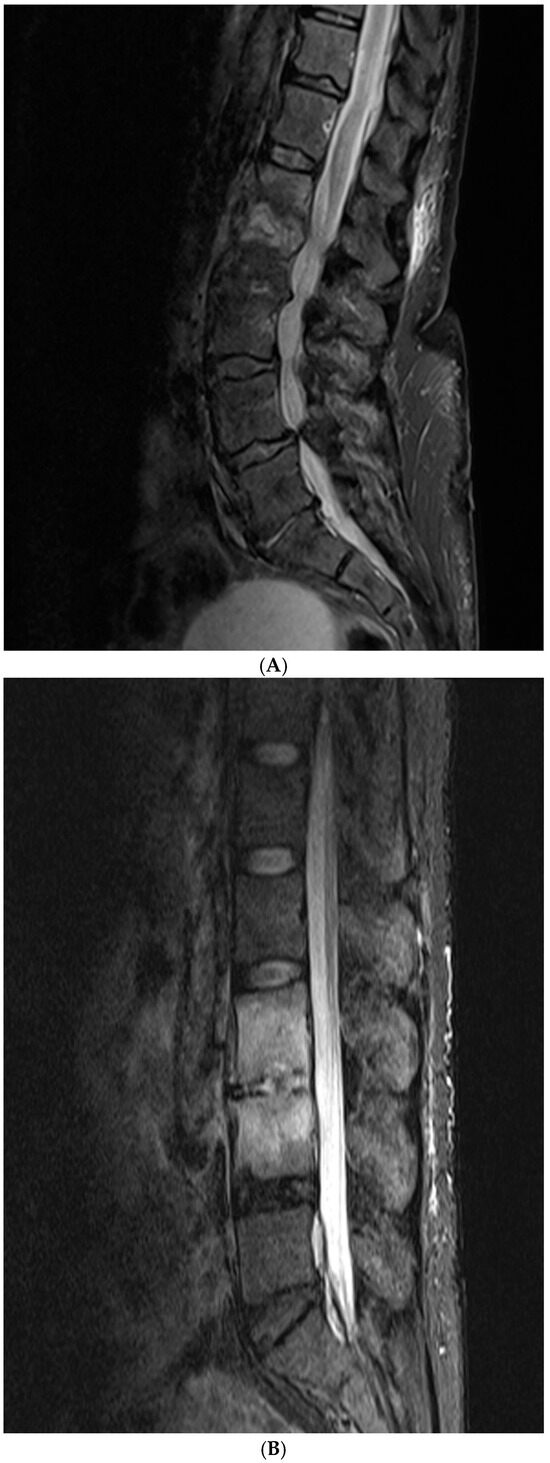

2.2. Imaging Scoring Systems

3.2. Analyses of Imaging Findings

4.2. Imaging Findings